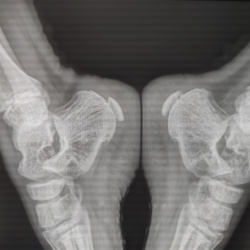

Возраст 9 лет. Жалуется на боли в голеностопном суставе в при ходьбе. Перелома не вижу, но что думаете про апофиз пяточной кости и ростковую зоне б/берцовой кости, норма?

Пациента не видела. В направлении не очень поняла что написано, но вроде болезнь Хаглунда справа. Если я правильно помню, то хаглунда это деформация пяточного бугра, у...